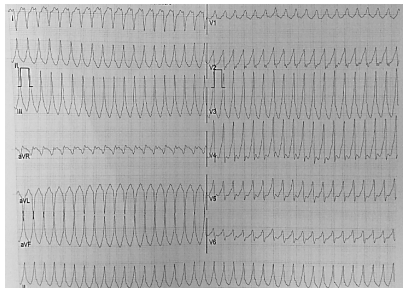

Paciente do sexo masculino, com doença de Chagas, apresenta taquicardia, sudorese, pressão arterial = 76x40mmHg, perfusão lentificada e se apresenta no pronto atendimento com o seguinte eletrocardiograma: